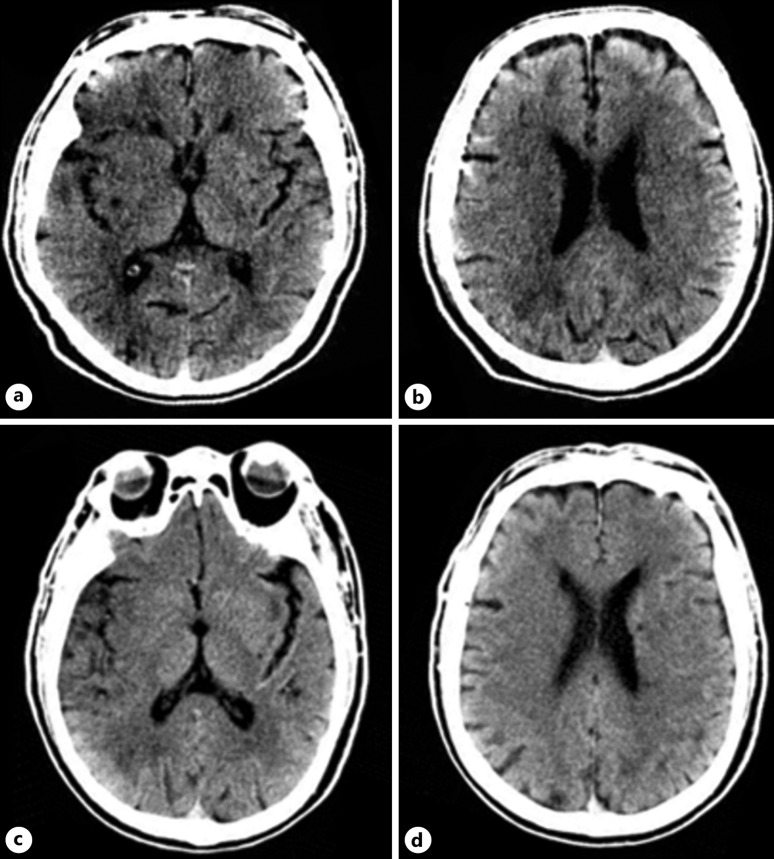

Case presentation: A 58-year-old male presented with a generalized tonic-clonic seizure. Emergent magnetic resonance imaging (MRI) revealed an extremely large infarction lesion in the right hemisphere with an Alberta Stroke Program Early Computed Tomographic Score (ASPECTS) value of 2 and occlusion of the terminal right internal carotid artery. The patient was immediately transferred to the Digital Subtraction Angiography (DSA) Unit for endovascular treatment with a stent retriever. After a rapid successful reperfusion with expanded treatment in cerebral infarction (eTICI) score of 3, the patient promptly recovered 24 h after the procedure. A brain MRI was repeated after 8 days of admission, and interestingly, the DWI lesion showed significant reversal. The modified Rankin scale (mRS) at discharge was 2 and 1 at 90-day follow-up, respectively.